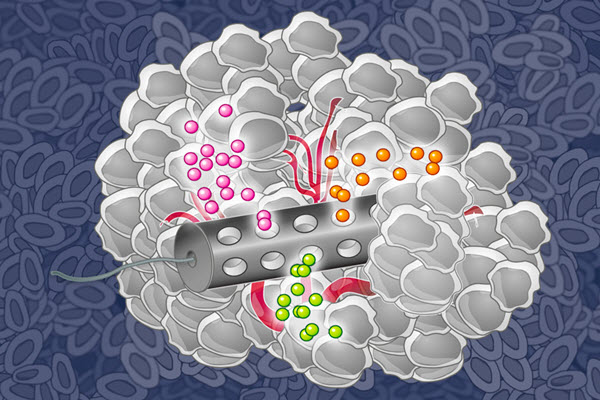

How to identify which cancer drugs work best for each patient

Implantable device could allow doctors to test cancer drugs in patients before prescribing chemotherapy